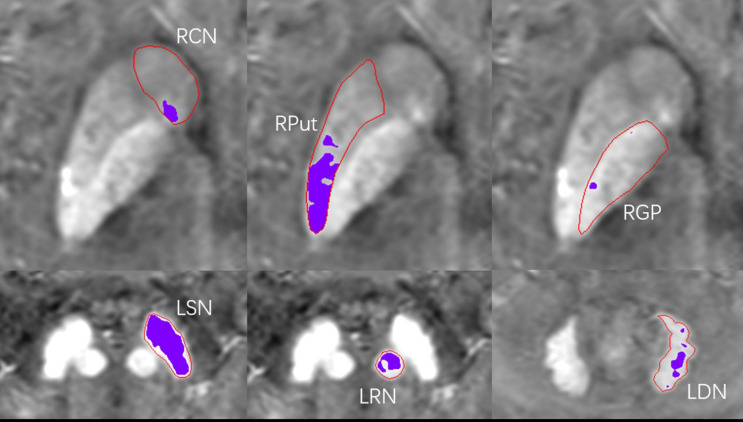

本研究旨在应用定量易感性制图(QSM)阈值法评估慢性肾脏疾病(CKD)患者灰质核铁沉积的变化,分析脑铁水平与认知功能的关系。前瞻性招募53例CKD患者,其中血液透析35例(HD, 57.54±10.42岁,男性21例),非血液透析18例(NHD, 55.06±11.47岁,男性10例),并与健康对照43例(HC, 55.67±7.79岁,男性18例)进行比较。所有参与者都进行了临床评估、神经心理测试和QSM扫描。测量了全核(MSVM、VM)和高铁区(MSVRII、VRII)的平均磁化率值(MSV)和体积。分析HD组QSM数据、神经心理评分与临床变量的相关性。采用线性回归分析探讨铁沉积对HD组认知和情绪幸福感的影响。p值为0.05,差异有统计学意义。HD患者右侧红核(RN)的MSVM高于hcc患者(P = 0.006)。此外,三组患者左尾状核(CN)、双侧壳核(Put)和右侧RN的MSVRII水平也存在显著差异(P = 0.027,经fdr校正)。左侧Put的MSVRII与肌酐、尿酸水平呈正相关,右侧Put的MSVRII与平均红细胞血红蛋白、平均红细胞血红蛋白浓度呈负相关。回归分析显示,左CN的铁沉积与抑郁独立相关,而左Put和右RN的铁沉积与延迟回忆表现独立正相关。相反,在控制了年龄、性别、受教育年限和透析时间后,双侧右侧和右侧RN的铁沉积与定向能力呈负相关。CKD患者的脑铁沉积通常过多且不均匀,特别是那些接受血液透析的患者。评估区域高铁沉积可以为铁的分布提供有价值的见解,这与认知功能障碍和情绪障碍有关。

This study aimed to evaluate changes in gray matter nuclei iron deposition in chronic kidney disease (CKD) patients using the quantitative susceptibility mapping (QSM) threshold method, and analyze the relationship between brain iron levels and cognitive function. A total of fifty-three CKD patients were prospectively recruited, comprising 35 hemodialysis (HD, 57.54 ± 10.42 years, 21 males) and 18 non-hemodialysis (NHD, 55.06 ± 11.47 years, 10 males ), and were compared to 43 healthy controls (HC, 55.67 ± 7.79 years, 18 males). All participants underwent clinical assessments, neuropsychological tests, and QSM scans. The mean magnetic susceptibility value (MSV) and volume of the whole nuclei (MSVM, VM) and high iron region (MSVRII, VRII) were measured. Correlations between QSM data, neuropsychological scores, and clinical variables in HD group were analyzed. Linear regression analysis was performed to explore the effect of iron deposition on cognition and emotional well-being in HD group. A statistically significant P-value was set at 0.05. HD patients exhibited higher MSVM in the right red nucleus (RN) compared to HCs (P = 0.006). Additionally, significant differences in the MSVRII were observed in the left caudate nucleus (CN), bilateral putamen (Put), and right RN among the three groups (all P = 0.027, FDR-corrected). MSVRII of the left Put was positively correlated with creatinine and uric acid levels, while the MSVRII of the right Put was negatively correlated with mean corpuscular hemoglobin and mean corpuscular hemoglobin concentration. Regression analysis revealed that iron deposition in left CN was independently associated with depression, while iron deposition in left Put and right RN were independently positively associated with delayed recall performance. Conversely, iron deposition in bilateral Put and right RN were negatively associated with orientation ability, after controlling for age, sex, years of education and duration of dialysis. Brain iron deposition is often excessive and uneven in CKD patients, particularly those undergoing hemodialysis. Assessing regional high-iron deposition can provide valuable insights into the distribution of iron, which is associated with cognitive dysfunction and emotional disorders.